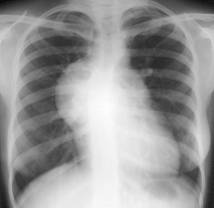

Anevrismele reprezinta dilatatii localizate ale aortei. Ele pot avea diferite forme: sacciforme, fusiforme, etc. Cel mai frecvent, sunt situate pe aorta ascendenta. Radiologic, apar ca o opacitate de forma ovala, de marime variabila, care face corp comun cu aorta, fiind situata in partea dreapta a opacitatii mediastinale in cazul situatiei pe aorta ascendenta si in partea stanga si posterior, atunci cand sunt situate pe aorta descendenta.

Conturul opacitatii este, in mod obisnuit, net, uneori este sters, neregulat in cazul unor reactii inflamatorii de vecinatate; opacitatea este omogenna, pulsatila; mai tarziu din cauza organizarii fibroase a cheagurilor si depunerii de saruri minerale, opacitatea devine neomogena si nepulsatila. Atunci cand anevrismele se dezvolta in apropierea unor formatiuni osoase, ele produc eroziuni (coloana vertebrala, stern, etc.).

Fig. 154 Diferite localizari ale anevrismelor aortice

Fig. 155 Anevrisme aorta toracica